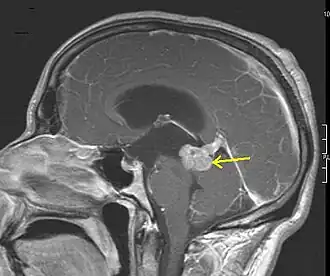

Die Bildgebung erfolgt in der Regel mittels Magnetresonanztomographie. Eine Kontrastmittelaufnahme ist bei Grad-2-Astrozytomen selten (20 %), bei höhergradigen Subtypen jedoch häufig. Verkalkungen können vorliegen. Insbesondere höhergradige Tumoren können auch ein umliegendes Ödem zeigen.[2][4][5]

Ein hochsensitives Merkmal für Astrozytome der Grade 2 und 3 ist ein T2/FLAIR-Mismatch, also ein Darstellungsunterschied zwischen zwei MRT-Sequenzen. In der T2-Sequenz zeigt sich der gesamte Tumorbereich hyperintens, also aufgehellt, während in der FLAIR-Sequenz nur der Randsaum hyperintens ist. In der T1-Sequenz ist der Tumor hypointens.[1][2][3][6]